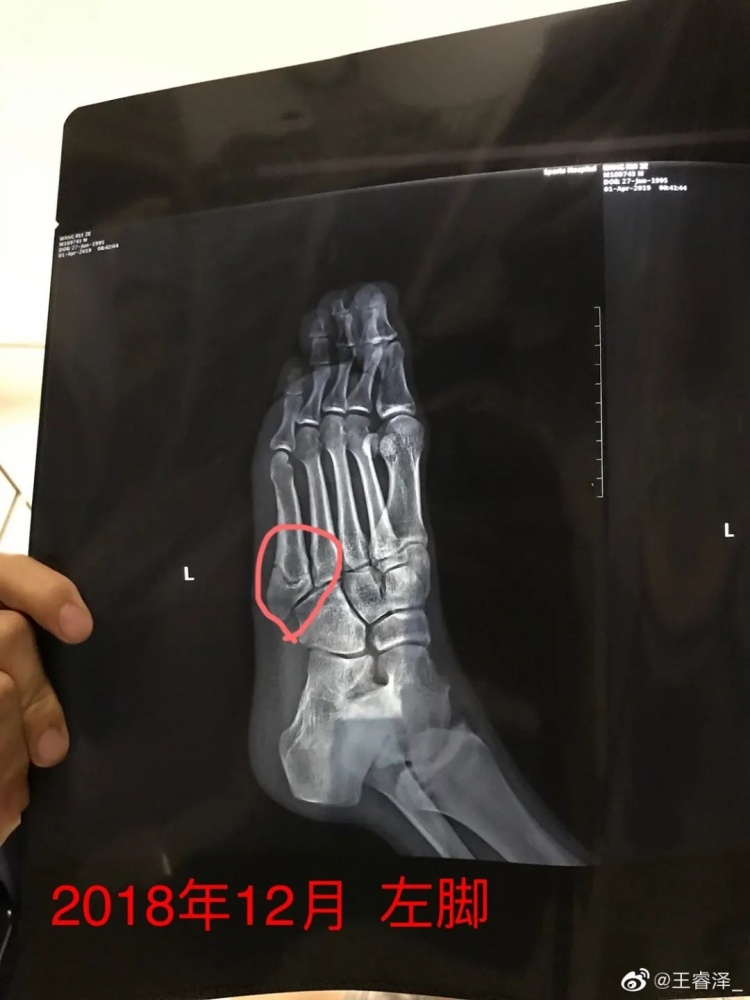

随着时间的推移,刘健越发觉得,王睿泽具备了打CBA的能力,并盘算着把他推荐到CBA俱乐部。就在这个时候,王睿泽的左脚出事了。据他回忆,最早只是“有点疼”,但歇几天就可以再打,他不知道,左脚的第五跖骨正在悄悄累积负荷,并最终在2018年底猝然崩折。

第五跖骨是组成足底的5根小型长骨当中最靠外的那根,在我看来,第五跖骨骨折很大一个特点就是容易复发。山西男篮葛昭宝、内蒙古女篮张茹都遭遇过这个情况,病程均超过了1年。而王睿泽最初并不懂这些,非但没有做手术,还穿着保护靴到处走,后来他才知道,患肢的每一次落地都可能会加重伤势。

王睿泽左脚第五跖骨骨折

也得说王睿泽确实“天赋异禀”,这个“造”法,伤情不仅没有恶化,反而逐渐好转——尽管片子始终显示骨头上有一道裂痕。他到擅长骨科的积水潭医院和北医三院去咨询,医生告诉他:“不疼的话就这么打,没事,做了手术也未必那么容易好。”于是,王睿泽开始康复训练,不到一个月后就出征了2019年附加赛,带着一张变得圆润的脸,3场比赛轰下66分,帮助球队打进了全国32强。